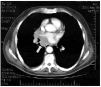

Fig. 2. Tomografía axial computarizada de tórax: masa mediastínica a nivel subcarinal (flecha) que infiltra esófago y bronquios.